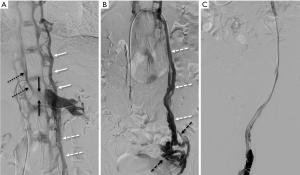

Due to a more minimally invasive nature, endovascular interventions have been applied to the treatment of NCS (Figure 9). Although no dedicated stent system has been developed solely for use in the renal vein, devices already on the market have been shown to be effective, including SMART Control (Cordis, Santa Clara CA, USA) and Wallstent (Boston Scientific, Marlborough MA, USA) (46,52,56). Though infrequent, endovascular stenting of posterior NCS has also been reported (58). It has been suggested that concomitant use of IVUS allows for more accurate sizing of stents (59). Benefits of this approach include rapid recovery time and symptom resolution. As with any intravascular stent, thrombosis is possible (though rare), and prevention requires anticoagulation and antiplatelet therapy for up to 3 months to allow for stent endothelialization (60). A study of 75 patients undergoing LRV stenting with mean 55 months follow-up identified a 6.7% rate of stent migration, either to the IVC [2], the right heart [2] or retrograde to the renal hilum [1], without significant variances in stent sizing or position to explain cause of migration (61). In a recent review of 18 cases of LRV stenting, primary patency was 85.2% at 2 years, however of five cases performed for stenosis after LRV transposition, three remained symptomatic despite stenting, suggesting limited utility as a salvage therapy (62).